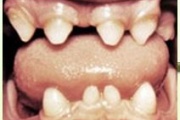

Vali sind huvitav pilt ja me näitame sellega seotud haigust ja sümptomeid